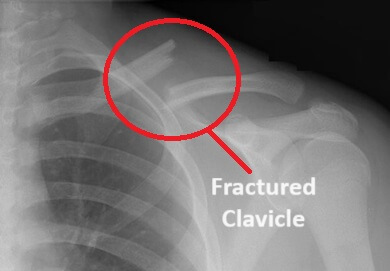

One of the most common causes of front shoulder pain in children is a fractured clavicle.

This is when there is a break in the collar bone at the front of the shoulder.

Clavicle fractures are usually caused by falling sideways or onto outstretched arm, an RTA, or a direct blow to the shoulder, but can also occur during birth

With clavicle fractures there is often a visible deformity, sharp front shoulder pain, a snapping noise with arm movements, decreased movement and sensation.